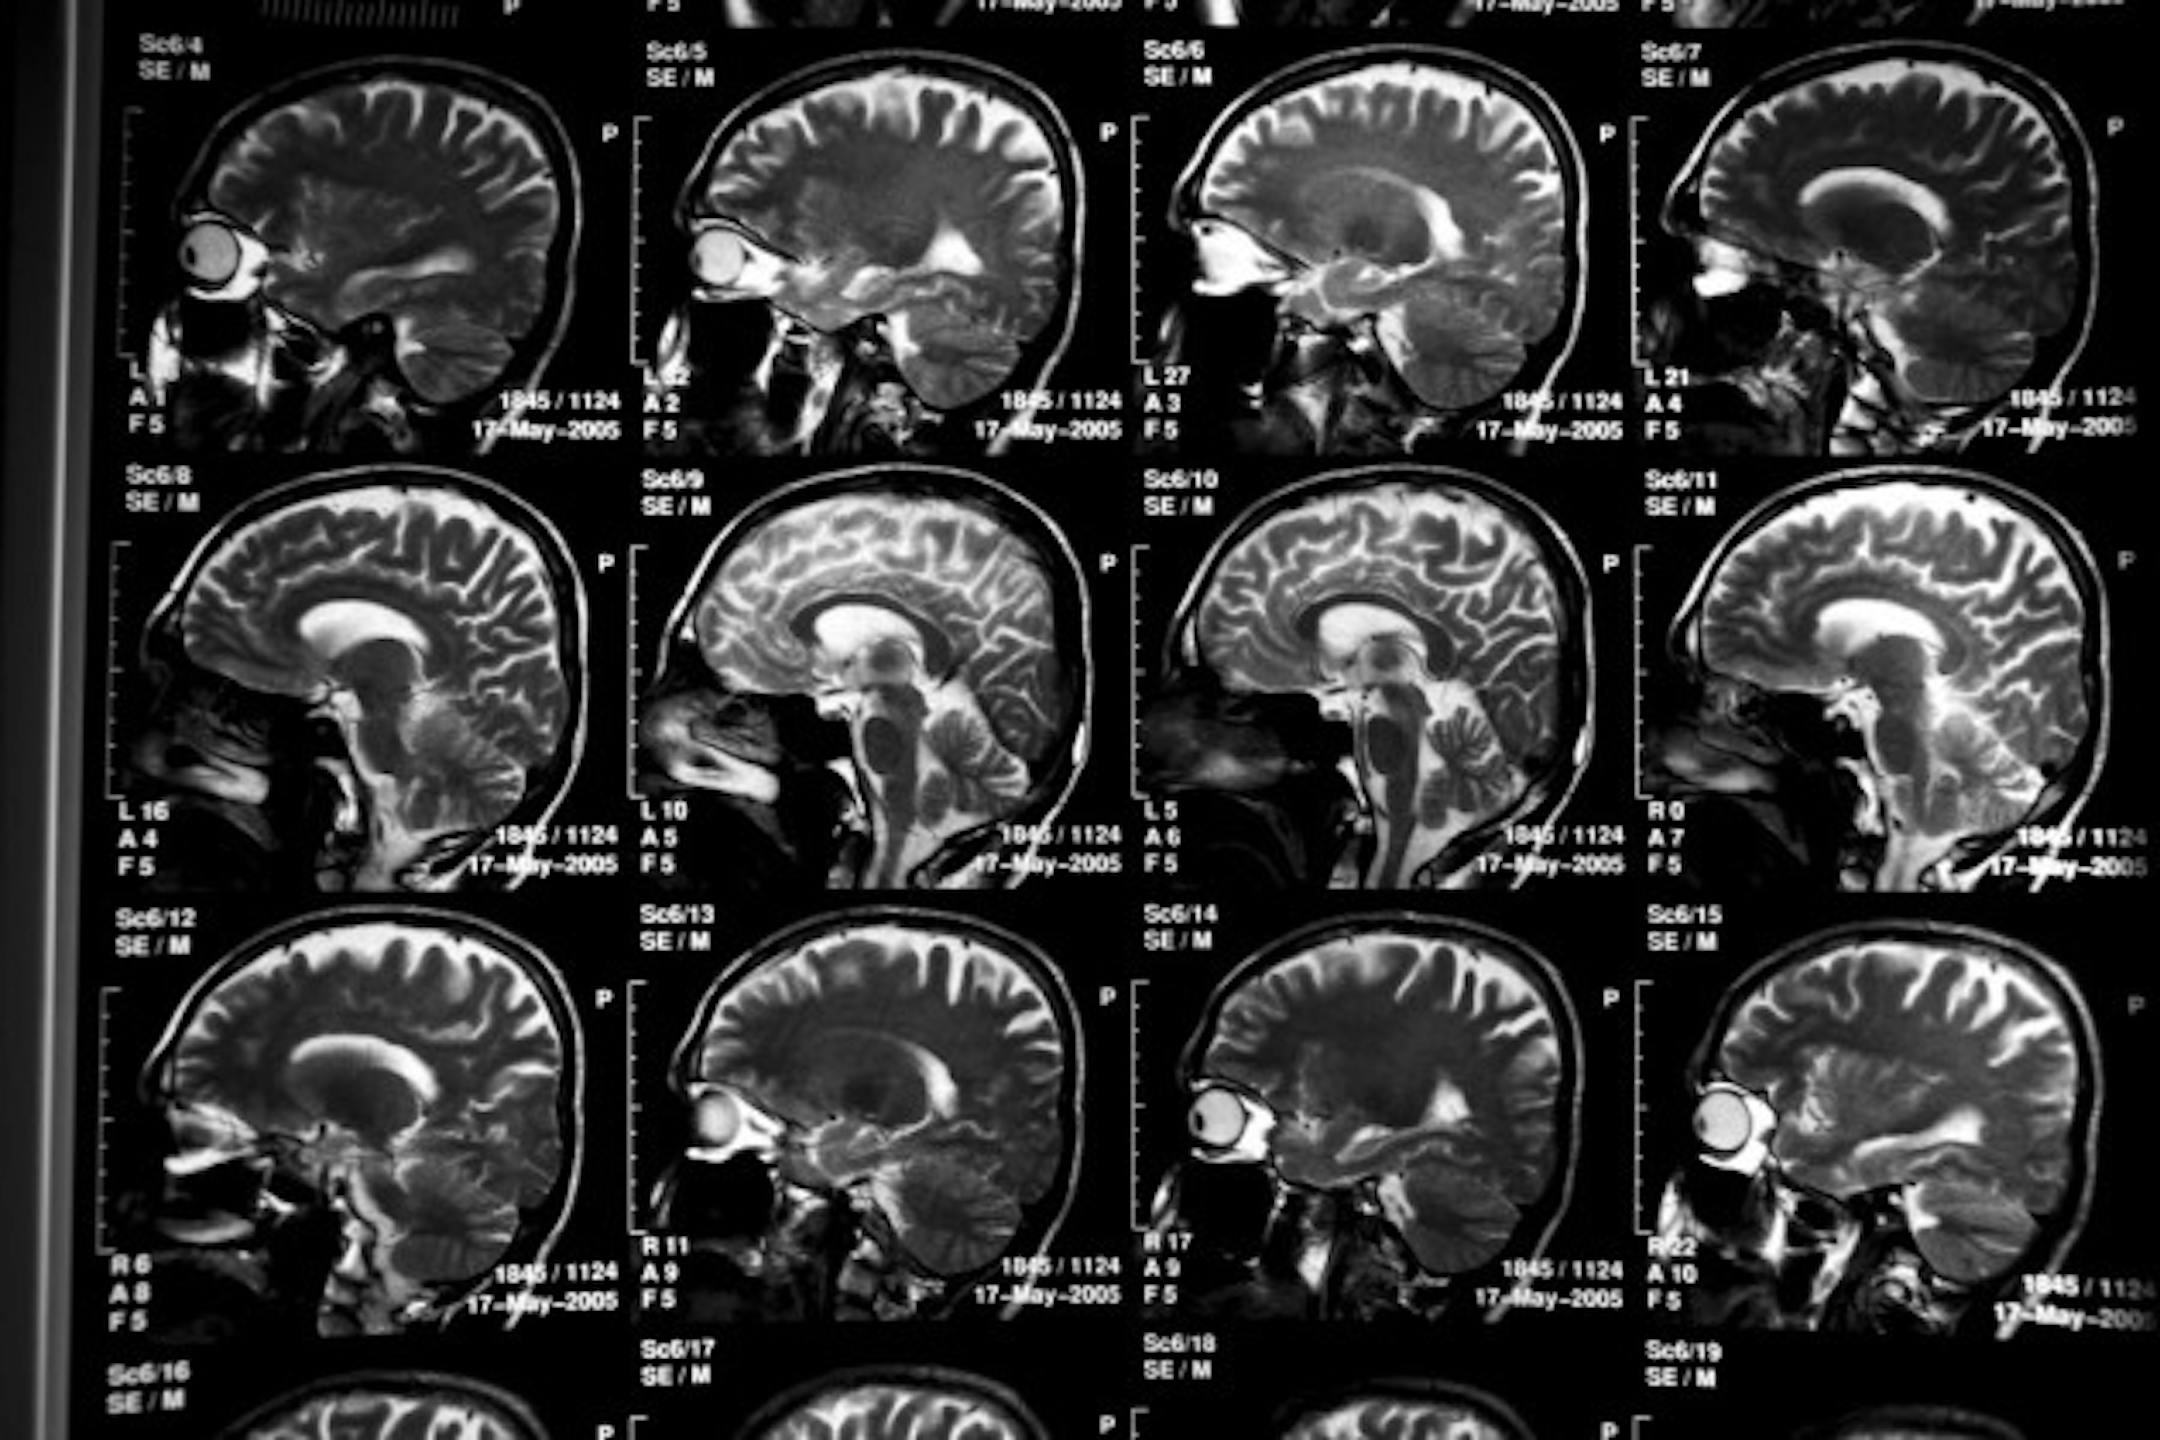

In the largest-ever genetic analysis of Alzheimer's, scientists have discovered 11 genes that may be tied to the late-onset form of the dementia disease.

Scientists scanned the brains of 74,076 older volunteers with Alzheimer's and others who did not have the disease in 15 countries to come up with their findings. The study was published in Nature Genetics.